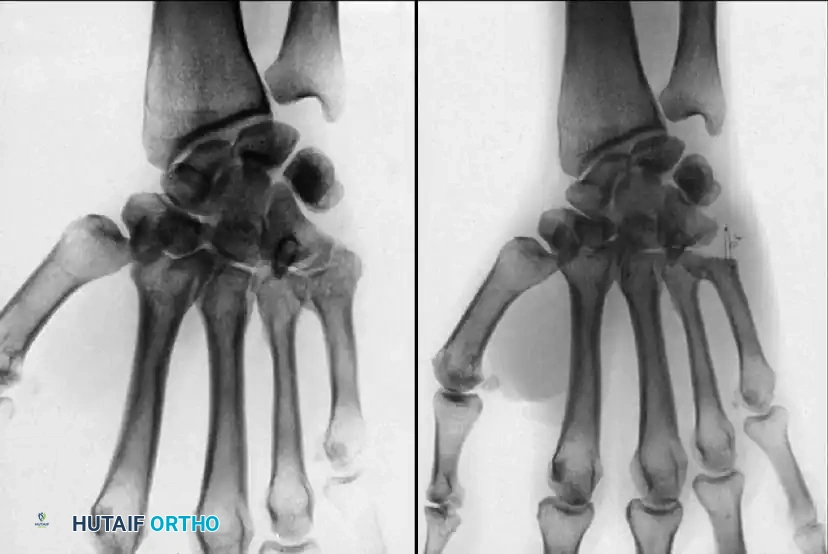

Fig. 64-31 Dislocation of fourth and fi fth carpometacarpal joints. A, Clinical appearance of hand before reduction. Note dorsoulnar hand swelling consistent with injury. B, Posteroanterior view. C, Lateral view. D, Oblique view. E and F, Traction was adequate to reduce, and splint was satisfactory to maintain reductions.

Standard posteroanterior (PA) radiographs may appear deceptively benign. The hallmark of a CMC dislocation on a PA view is the loss of the parallel joint surfaces (the "M" line) at the carpometacarpal articulations.

A true lateral radiograph is an absolute necessity for accurate diagnosis, as it will clearly demonstrate the dorsal or volar displacement of the metacarpal bases relative to the carpal row.

Oblique views further delineate the extent of articular comminution and subluxation.

When identified acutely, manual reduction via longitudinal traction and direct pressure over the metacarpal bases is often easily achieved. However, the injury is inherently unstable.

Kirschner wire (K-wire) fixation is almost universally required to prevent redislocation.